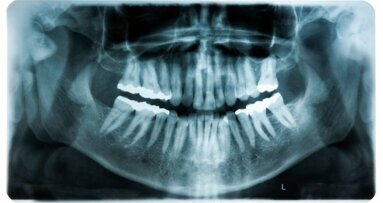

De meest unieke mogelijkheid binnen Qlinix is het consulteren. Met een consult kan een Qlinix-gebruiker een klinische casus, hypothese of praktijkvraag voorleggen aan een individuele collega of expert, of aan een groep die zich richt op hetzelfde onderwerp. “Deze optie is vergelijkbaar met wanneer je als tandarts een collega belt om een ingewikkelde patiënt te bespreken, maar dan online,” verklaart Theunissen. Het consult kan worden uitgebreid met beeldmateriaal, zoals foto’s en röntgenopnamen. De beslotenheid van het platform garandeert dat een casus veilig en enkel met BIG-geregistreerde professionals wordt besproken. Theunissen benadrukt: “Qlinix is een veilige community voor en door vakgenoten.” Door de mogelijkheid van het online consult heeft Qlinix zeker een rol in de dagelijkse praktijk van de tandarts, denkt Theunissen. “Voor een telefonisch consult moeten beide partijen op hetzelfde moment tijd hebben, en je kunt niet altijd van tevoren inschatten hoeveel tijd ervoor nodig is. Soms wil je er ook even rustig over nadenken.”